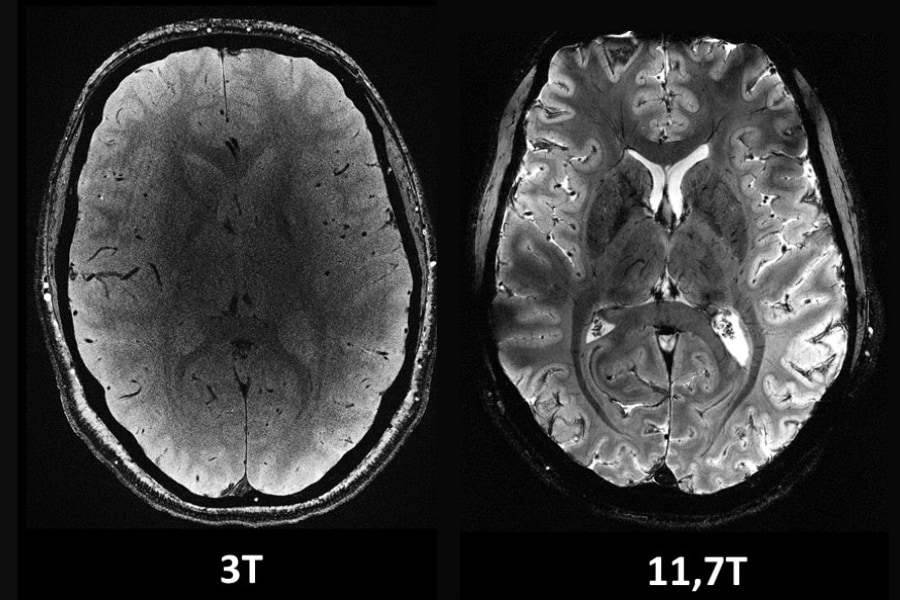

FSLを用いたシェルスクリプト演習:脳3次元T1強調MRIの水平断